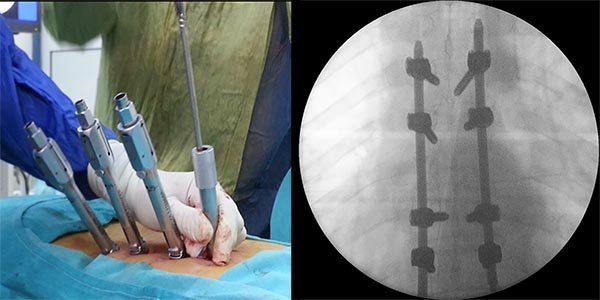

Figura 5:

Caso 8. Se realizó una estabilización percutánea T6-T10. El paciente retornó a UTI, para estabilizar su cuadro respiratorio y hemodinámico.

Este tipo de cirugía permite colocar tornillos transpediculares en forma percutánea, y unir los mismos mediante barras de titanio. Esto cumple la función de “tutor interno”, que estabiliza en forma inmediata la lesión, permitiendo la movilización, aliviando el dolor y logrando un ambiente propicio para la consolidación de las fracturas.

El avance de la tecnología en los implantes, permite en la actualidad realizar maniobras de distracción y compresión sobre los tornillos, logrando mejores correcciones en los planos sagital y coronal, y posibilita en algunos casos realizar una “descompresión indirecta” del canal espinal mediante el fenómeno de “ligamentotaxis”.1